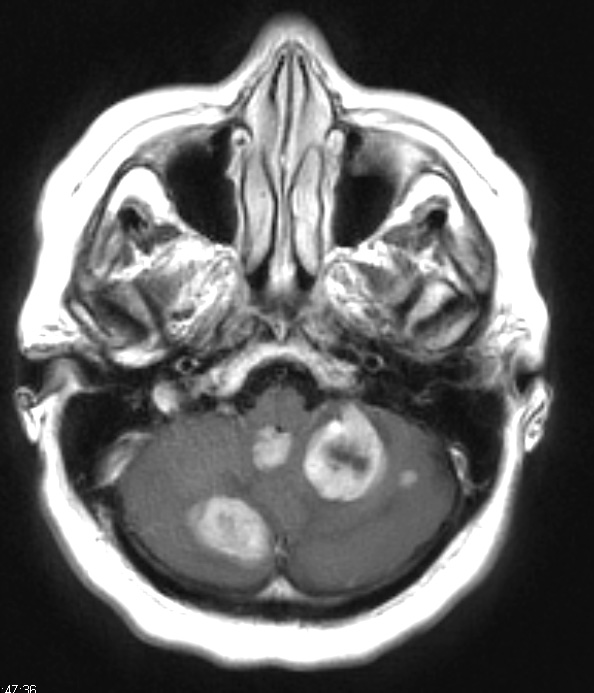

Case 18 History Metastatic ovarian carcinoma ---- The patient is a 62 year old woman with disseminated peritoneal ovarian carcinoma with pleural metastasis presenting with multiple brain masses. Operative procedure: Posterior fossa craniotomy with tumor resection. ---- 18A Numerous metastatic lesions are found in the cerebellum in this T1-weighted scan with contrast.